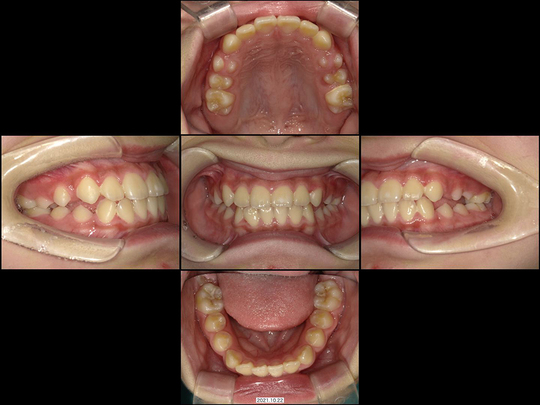

Mさん 開始時9歳 女性

矯正前

画像をクリックで拡大

矯正後

上下の前歯がガタガタで、中学生になってから抜歯するしかない。それまでは様子を見ましょうと言われたケースです。当院での治療スタート時が1期治療後半の時期であり、一般的には対応は困難かと思われる状態でした。

ところが精査の上、あごの骨年齢的にまだ拡大可能であることが判明。ワイヤー矯正なし、通常通りの固定式拡大装置の非抜歯矯正で対応しました。

治療の期間・回数

36か月、36回

​費用

576,400円